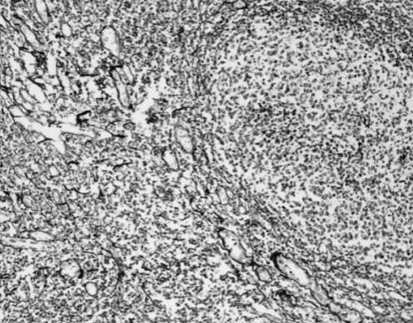

SPECIAL STAINS